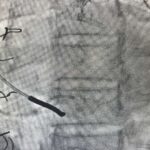

Zabieg wykonywany jest z nakłucia żyły szyjnej i polega na kontrolowanym zwężeniu zatoki wieńcowej przy użyciu rozprężalnego na balonie stentu o kształcie klepsydry. Wskutek zabiegu dochodzi do stopniowego zwężenia pola przepływu przez zatokę wieńcową z redystrybucją przepływu krwi z obszarów o lepszym do obszarów o gorszym ukrwieniu mięśnia sercowego.